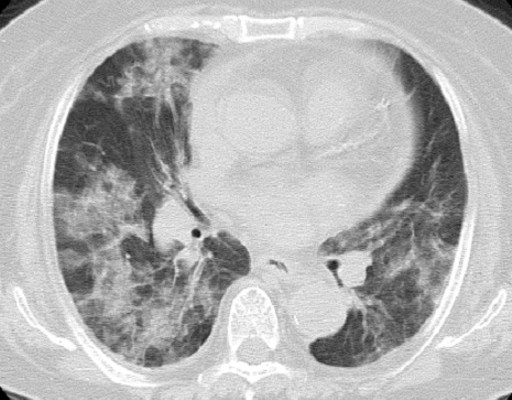

A 74-year-old woman was referred to our hospital with a 23x19 mm pancreatic body tumor with dilatation of pancreatic duct which was detected incidentally and was diagnosed with pancreatic cancer. It was clinically staged as T3N0 Stage II (UICC) and a distal pancreatectomy was then planned. However, the resection was discontinued due to peritoneal dissemination, and only a biopsy of the tumor was performed. The postoperative course was uneventful, but multiple liver metastases were found in a follow-up CT scan. Laboratory data showed the following levels: white blood cell count 10,200 mm-3 (WBC; reference range: 4,000-9,000 mm-3), C-reactive protein 1.07 mg/dL (CRP; reference range: 0-0.5 mg/dL), aspartate aminotransferase 60 IU/L (AST; reference range: 0-35 IU/L), alanine aminotransferase 59 IU/L (ALT; reference range: 0-40 IU/L), lactate dehydrogenase 259 U/L (LDH; reference range: 119-229 U/L), blood urea nitrogen 9 mg/dL (BUN; reference range: 8-20 mg/dL), and creatinine 0.66 mg/dL (reference range: 0.6-1.2 mg/dL). Soon after the CT scan, she began chemotherapy with gemcitabine 1,000 mg/m2 on days 1, 8, and 15 every 28 days. After her fourth course of the chemotherapy, she developed shortness of breath, and was dyspneic at rest. There was no finding of heart failure or evidence of a pulmonary embolism. A chest CT showed bilateral diffuse ground-glass opacities in both lungs (Figure 1). The radiological features seemed compatible with acute interstitial pneumonitis. An echocardiogram was normal. Laboratory data showed WBC 10,500 mm-3, CRP 9.46 mg/dL, AST 22 IU/L, ALT 15 IU/L, LDH 357 U/L, BUN 14 mg/dL, creatinine 0.54 mg/dL, and CA 19-9 348,440 U/mL (reference range: 0-37 U/mL). There was no elevation of antibody titers of Mycoplasma, Legionella pneumophilia, and Chlamydia psittaci. Antibiotic treatment was initiated with ciprofloxacin on admission; however, her respiratory status rapidly deteriorated. Suspecting gemcitabine-induced pneumonitis, the gemcitabine was discontinued and the patient was treated with methylprednisolone (500 mg/day) for 3 days. A lung biopsy was planned but the patient’s respiratory condition improved after steroid therapy, so the procedure was not performed. On the 21st day of hospitalization, a chest CT showed the disappearance of the diffuse ground-glass opacities in both lungs (Figure 2). The steroids were gradually tapered off. Due to concerns of gemcitabine-induced pulmonary pneumonitis, the chemotherapy was changed to S 1 combination monotherapy.

Figure 1. Chest CT on admission showing bilateral diffuse ground-glass opacities in both lungs. |